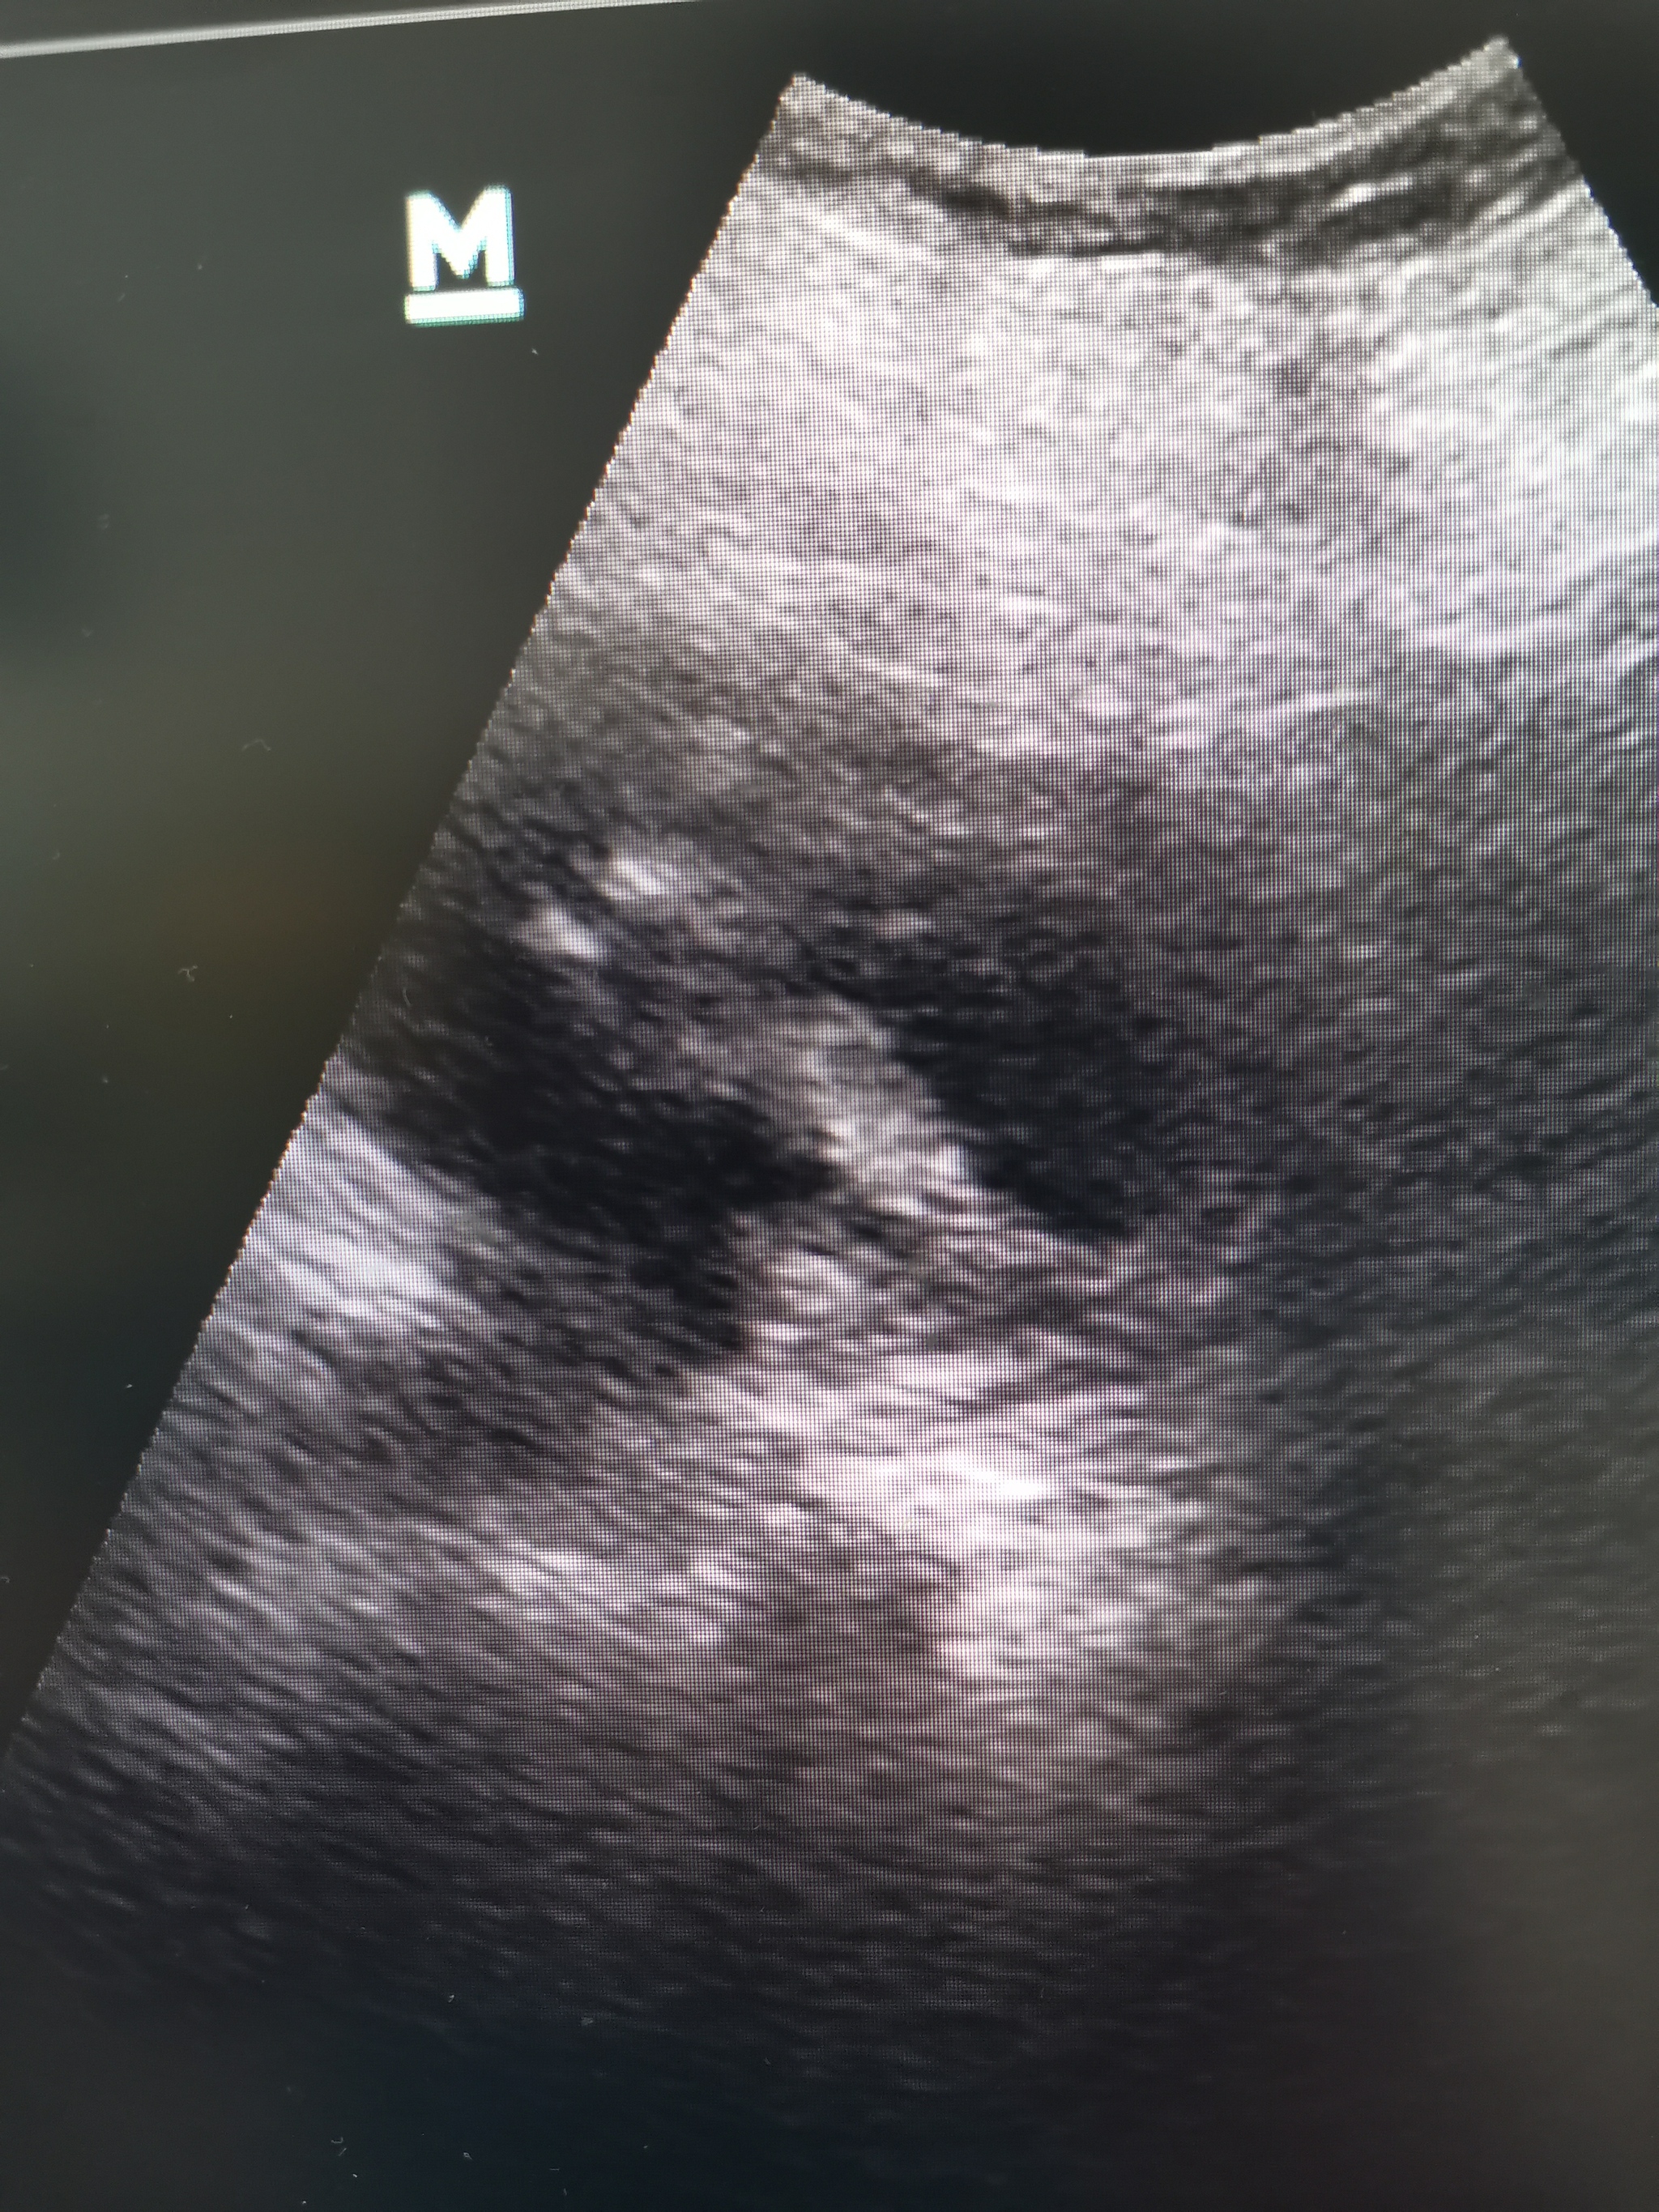

На УЗИ видны вполне обычные почки (не стал фоткать), а по нижнему сегменту левой почки гетерогенное, солидно-кистозное, отграниченное, с ровным, не чётким, гипоэхогенным контуром образование около 6 см (см фото).

В подобной ситуации может быть несколько интерпретаций: нагноившаяся киста почки (полость с гнойной мочой), рак, карбункул (гнойник на почке).